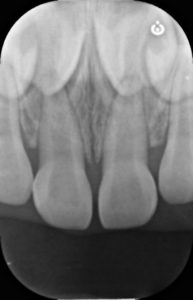

受傷直後

年齢:3歳女の子

30分前にこけて上の前歯を強打し、この写真からはわかりませんが、上の前歯の位置異常(脱臼)が生じています。

参考症例 外傷により右上前歯の脱臼が生じています

乳歯の形態には異常はなく、打った歯の位置が変わっているため元の位置に整復し、ワイヤーで固定を行います。

脱臼した左上乳中切歯を整復し、両隣の歯とワイヤーで固定します。

脱臼した歯は一度骨から剥がれているため、周囲の骨とくっつくまでこの状態で経過観察をしていきます。